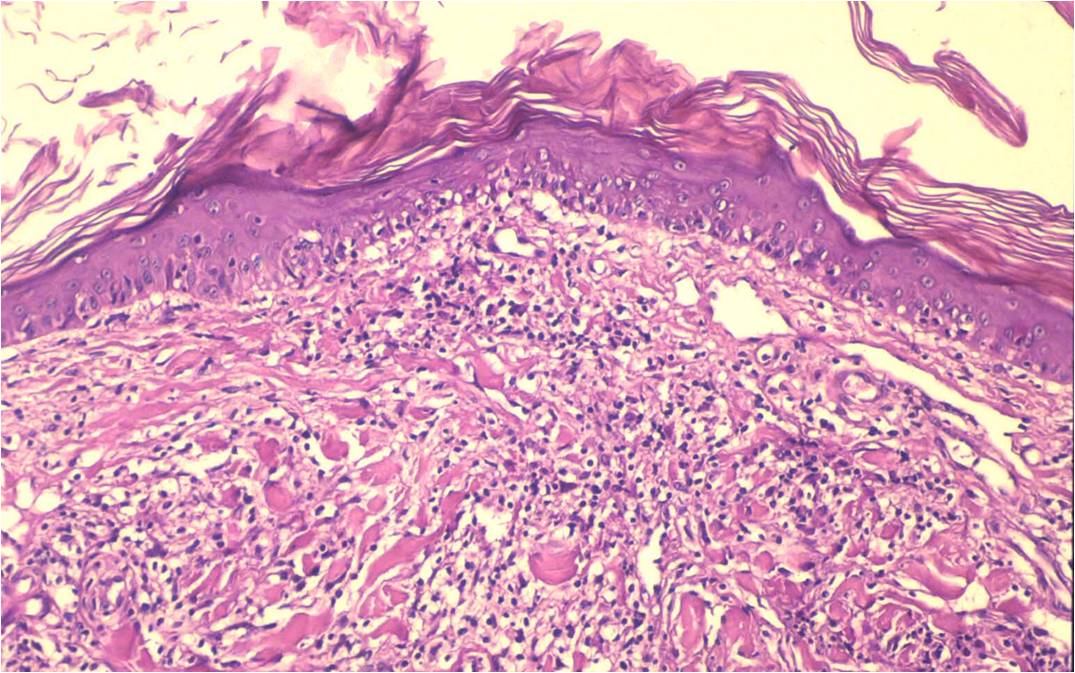

La demodicosis en el hámster casi siempre va asociada a una enfermedad subyacente. Se decidió realizar una biopsia de las placas indurativas ante la sospecha de que pudiera haber una neoplasia asociada. El  resultado de la biopsia fue el siguiente: Presencia de ácaros del Gº Démodex en los folículos dilatados (Figura 4). Infiltrado en la dermis de células mononucleares (linfocitos y células plasmáticas). La tinción con CD4+ identifica a una población de linfocitos de carácter neoplásico (Figuras 5 y 6).

Figura 4